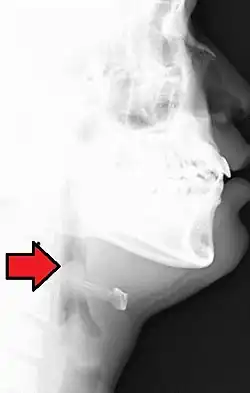

L'épiglottite est un type de laryngite pouvant constituer une urgence vitale chez l'enfant et consistant en un œdème de l'épiglotte obstruant les voies aériennes supérieures.

Elle se manifeste par une dyspnée de type laryngée, de survenue rapide dans un contexte fébrile chez l'enfant : essentiellement inspiratoire, avec stridor, dysphonie (altération de la voix).